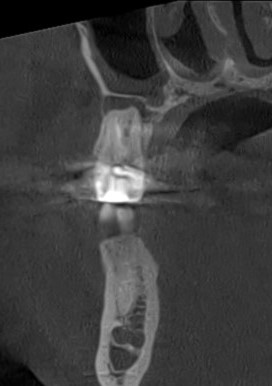

Клинические случаи в эндодонтии